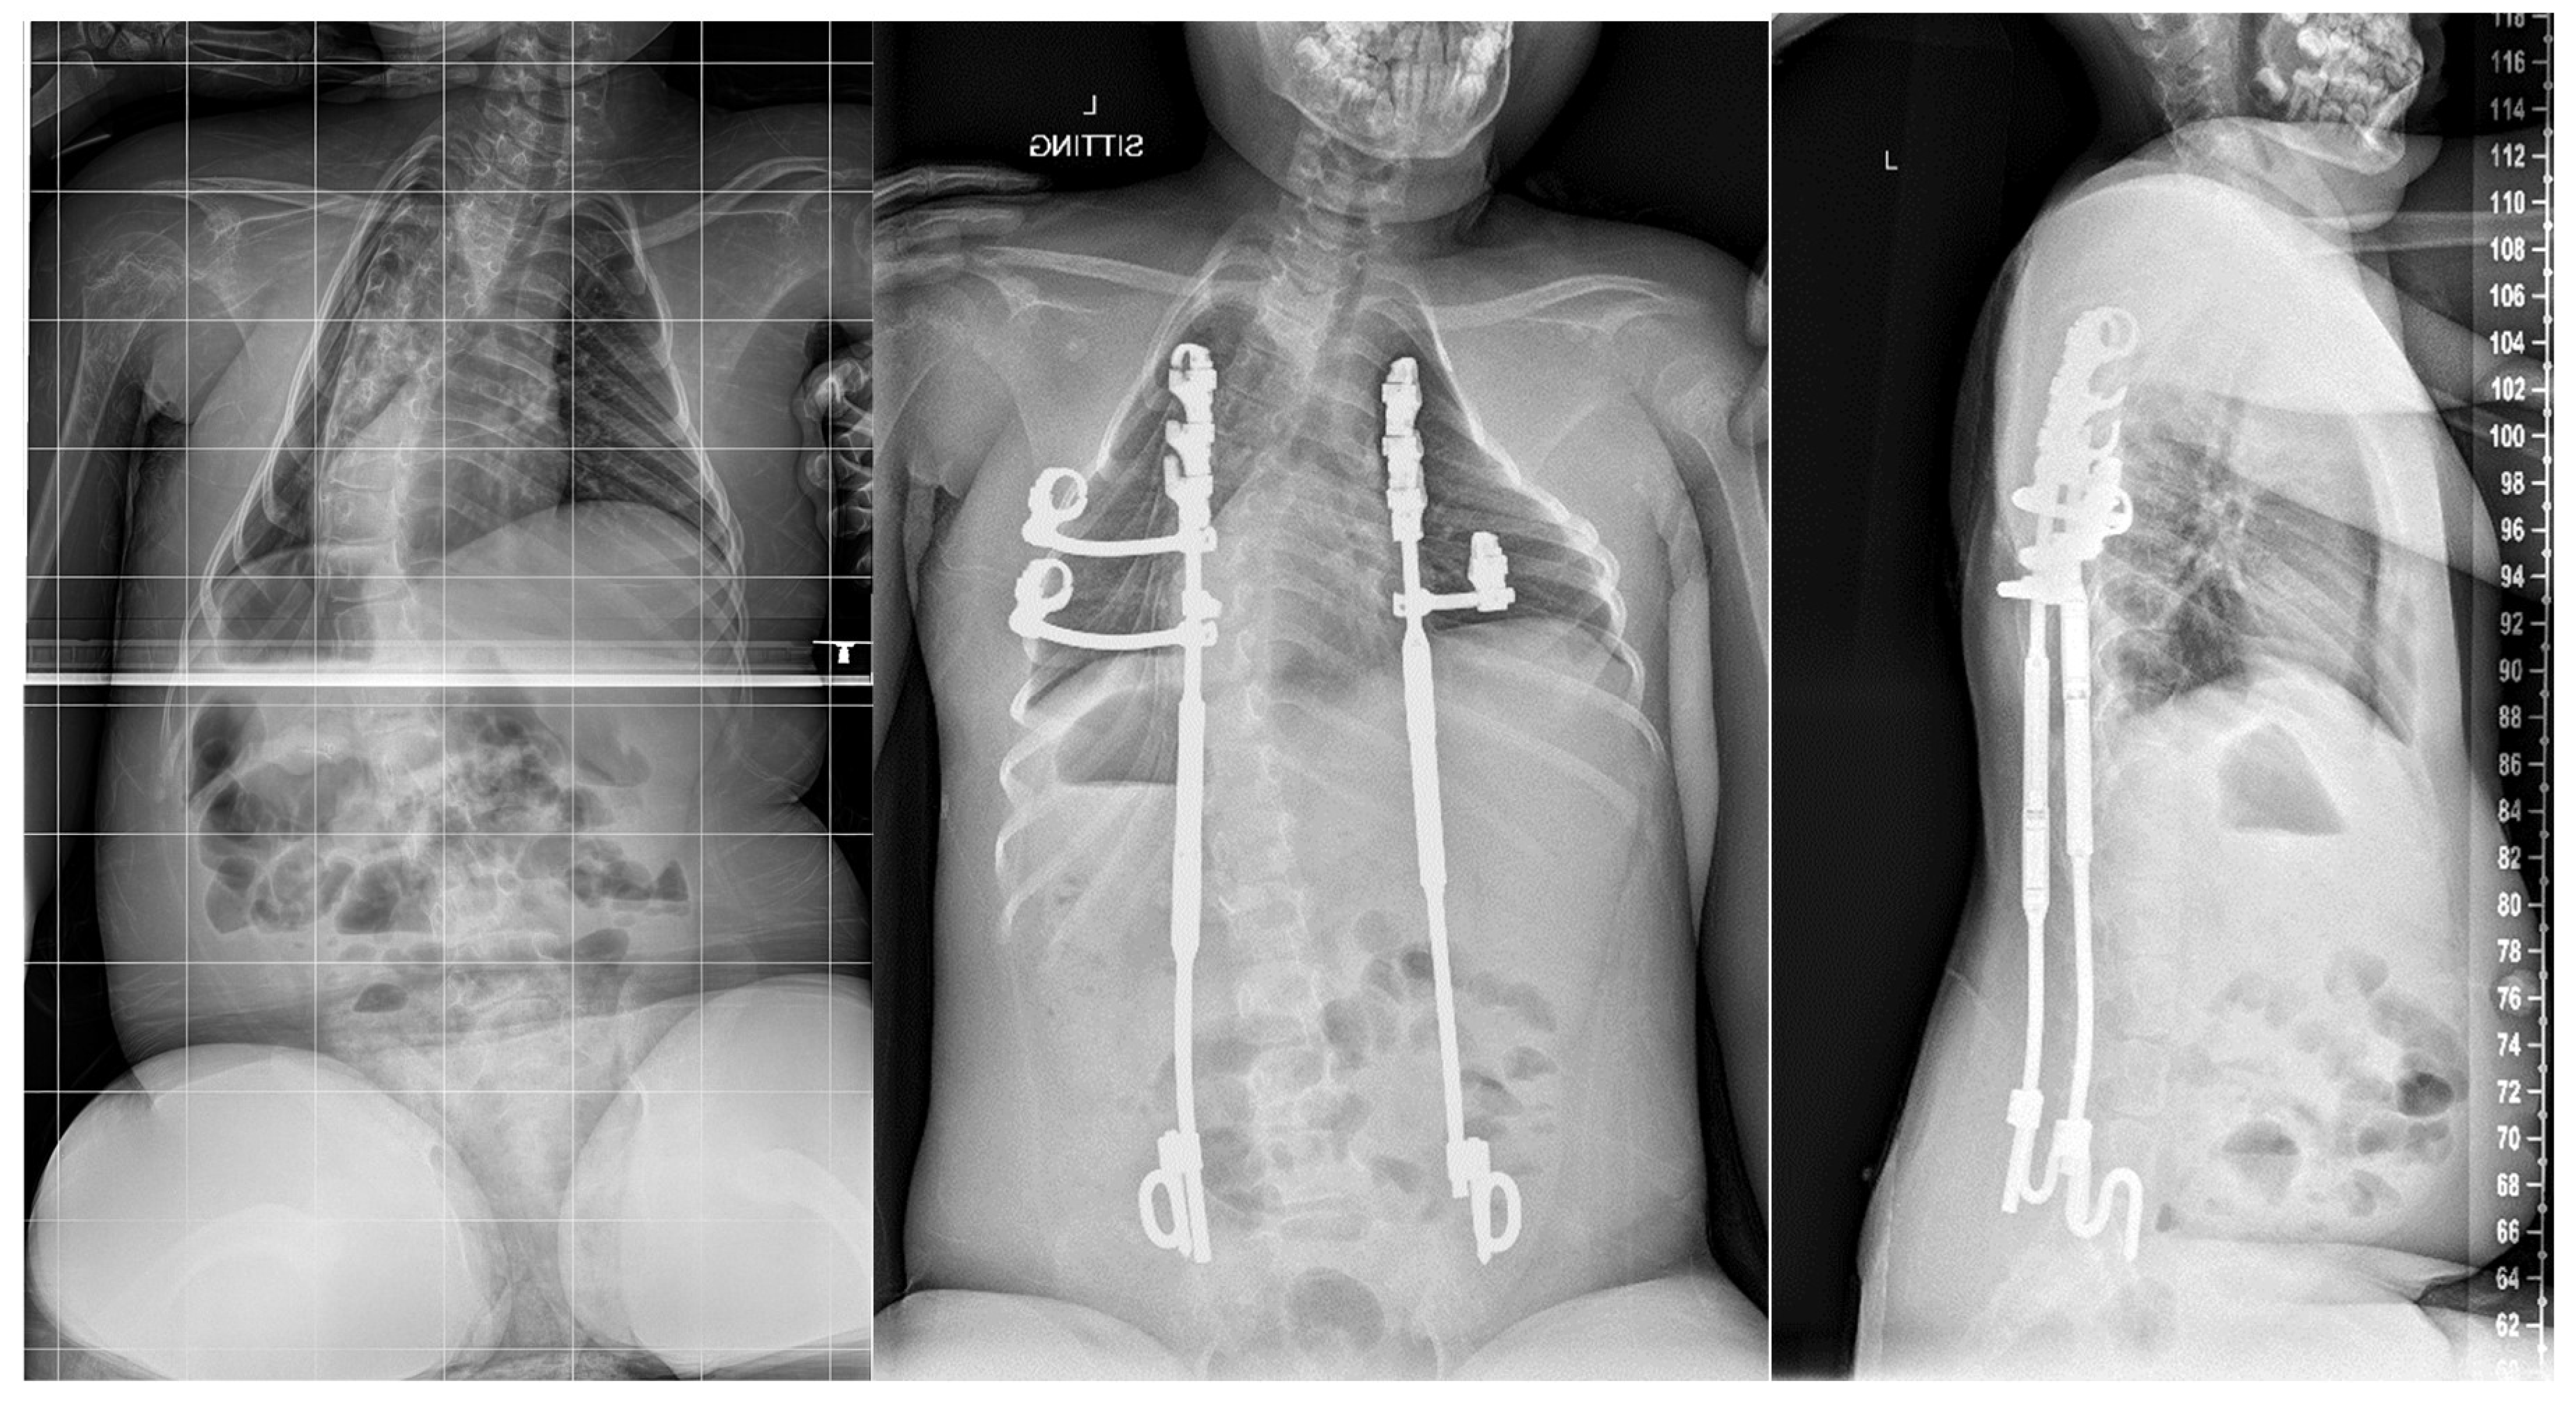

- Akbarnia, B.A.; Marks, D.S.; Boachie-Adjei, O.; Thompson, A.G.; Asher, M.A. Dual Growing Rod Technique for the Treatment of Progressive Early-Onset Scoliosis: A Multicenter Study. Spine 2005, 30, S46. [Google Scholar] [CrossRef] [PubMed]

- Akbarnia, B.A.; Breakwell, L.M.; Marks, D.S.; McCarthy, R.E.; Thompson, A.G.; Canale, S.K.; McCarthy, J.J.; Sponseller, P.D. Dual Growing Rod Technique Followed for Three to Eleven Years Until Final Fusion: The Effect of Frequency of Lengthening. Spine 2008, 33, 984–990. [Google Scholar] [CrossRef]

- Thompson, G.H.; Akbarnia, B.A. Single and Dual Traditional Growing Rods. In The Growing Spine: Management of Spinal Disorders in Young Children; Springer: Berlin/Heidelberg, Germany, 2016; pp. 645–668. [Google Scholar] [CrossRef]

- Hell, A.K.; Groenefeld, K.; Tsaknakis, K.; Braunschweig, L.; Lorenz, H.M. Combining Bilateral Magnetically Controlled Implants Inserted Parallel to the Spine With Rib to Pelvis Fixation: Surgical Technique and Early Results. Clin. Spine Surg. 2018, 31, 239–246. [Google Scholar] [CrossRef] [PubMed]

- Heyer, J.H.; Anari, J.B.; Baldwin, K.D.; Mitchell, S.L.; Flynn, J.M.; Sankar, W.N.; Campbell, R.M.; Smith, J.T. Rib-to-spine and rib-to-pelvis magnetically controlled growing rods: Does the law of diminishing returns still apply? Spine Deform. 2023, 11, 1517–1527. [Google Scholar] [CrossRef]